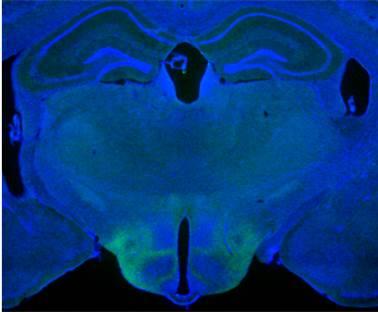

Damage or lost function in the animals' midbrain wall structure -- the lateral septum -- was found to trigger a cascade of activity in other brain regions that produced "septal rage." These sudden, violent acts, mostly attacks on other mice, have long been seen in rodents with a damaged lateral septum, and in some birds, researchers say.

The lateral septum, Lin notes, is physically connected to, and receives electrical signals from, the part of the brain that controls emotion and learning (the hippocampus). The lateral septum also projects into and receives signals from the brain region most broadly tied to aggression and hormone production (the hypothalamus).

Among the study's key findings was that stimulating brain cells in the lateral septum controlled other brain cells, notably in a centrally located region of the hypothalamus, identified anatomically as the ventrolateral part of the ventromedial hypothalamus. Previous research by Lin had shown this brain region to be highly active during natural aggression but, until now, had not identified the other parts of the brain that interact with it in this context.